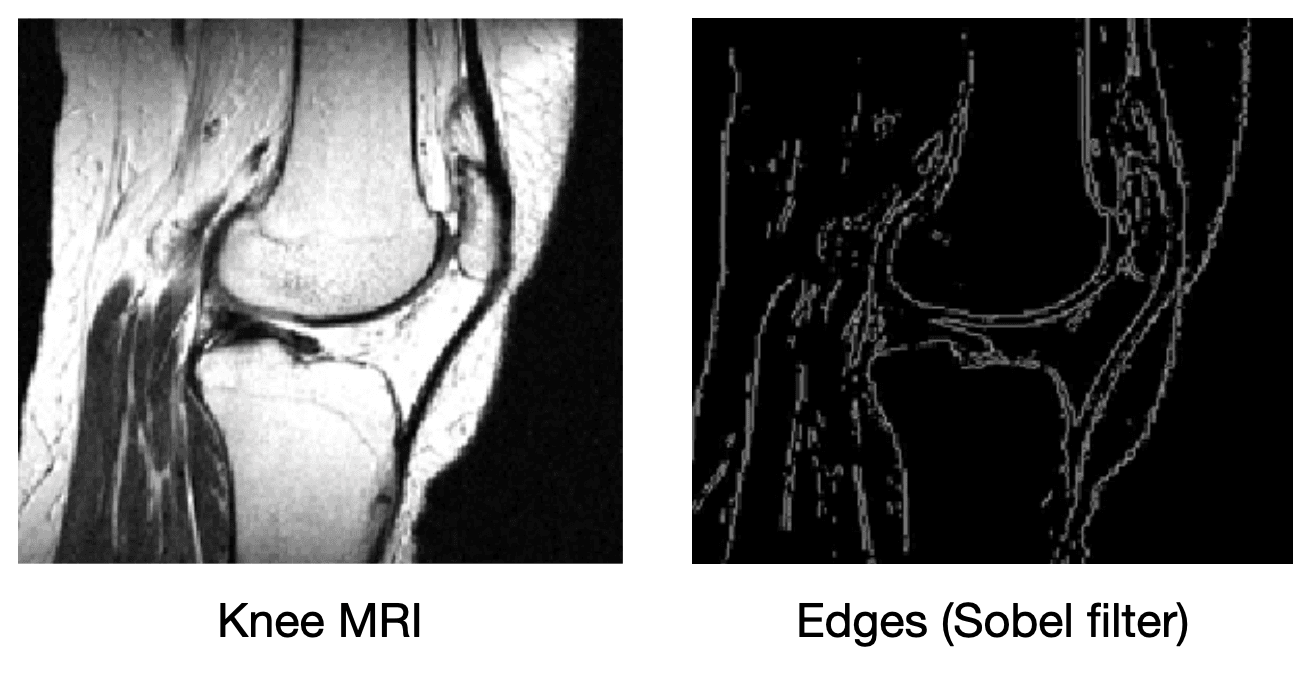

What if we add more information to the image reconstruction process that is not from the current measurement ? For example, in compressed sensing, we can assume that the desired image doesn't have many edges (i.e., that we can "compress" the edges). Here's a knee MRI along with its edge map, which we see is very sparse:

How do we incorporate the fact that we know that MRI images aren't supposed to have many edges? First, we need some way of counting how many edges are in an MRI image. Edges are places in the image with high spatial derivatives, so a decent way to count edges is by summing the spatial derivatives (this is called the total variation, and we can write this mathematically as , where is the spatial gradient and is the L1 norm).